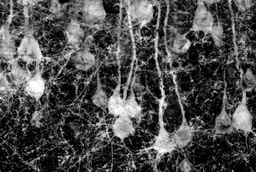

In addition, using brain slice electrophysiological techniques, we recorded the changes in synaptic transmission and the neuronal firing rates under the stress model and the transgenic model, respectively, and verified that the regulatory effect of metformin on neurons is dependent on AMPK. The regulatory effect of AMPK on the firing of GABAergic interneurons played a crucial role in anxiety behaviors and action of metformin. Our work unraveled the regulatory effect of metformin on neurons and expanded the functional studies of the energy metabolism sensor-AMPK in neurons.